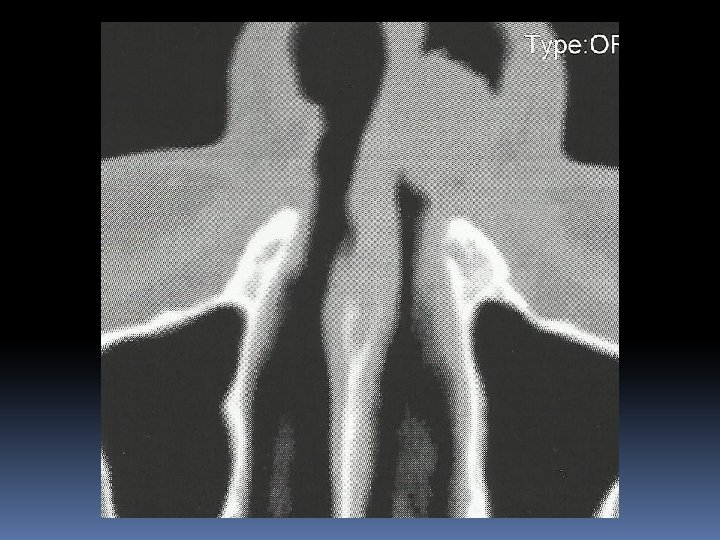

Case Report Paziente di sesso maschile, a. 58, in buona salute Ostruzione nasale omolaterale Neoformazione polipoide carnosa con mucosa integra che occlude anteriormente la fossa nasale sinistra

Intervento chirurgico: asportazione della neoformazione impiantata sulla testa del turbinato inf. in blocco con testa, corpo e parte della coda del turbinato, i margini di resezione appaiono macroscopicamente indenni

Referto istopatologico Neoformazione polipoide impiantata sulla testa del turbinato inferiore, diametro cm. 1 x 2, al taglio appare di colorito biancastro, solida e consistente. Reperti istologici ed immunoistochimici compatobili con melanoma della mucosa della fossa nasale, negativi i limiti di resezione. Sono state eseguite colorazioni con S 100, MART – 1 e HMB 45. Indice di proliferazione 3%